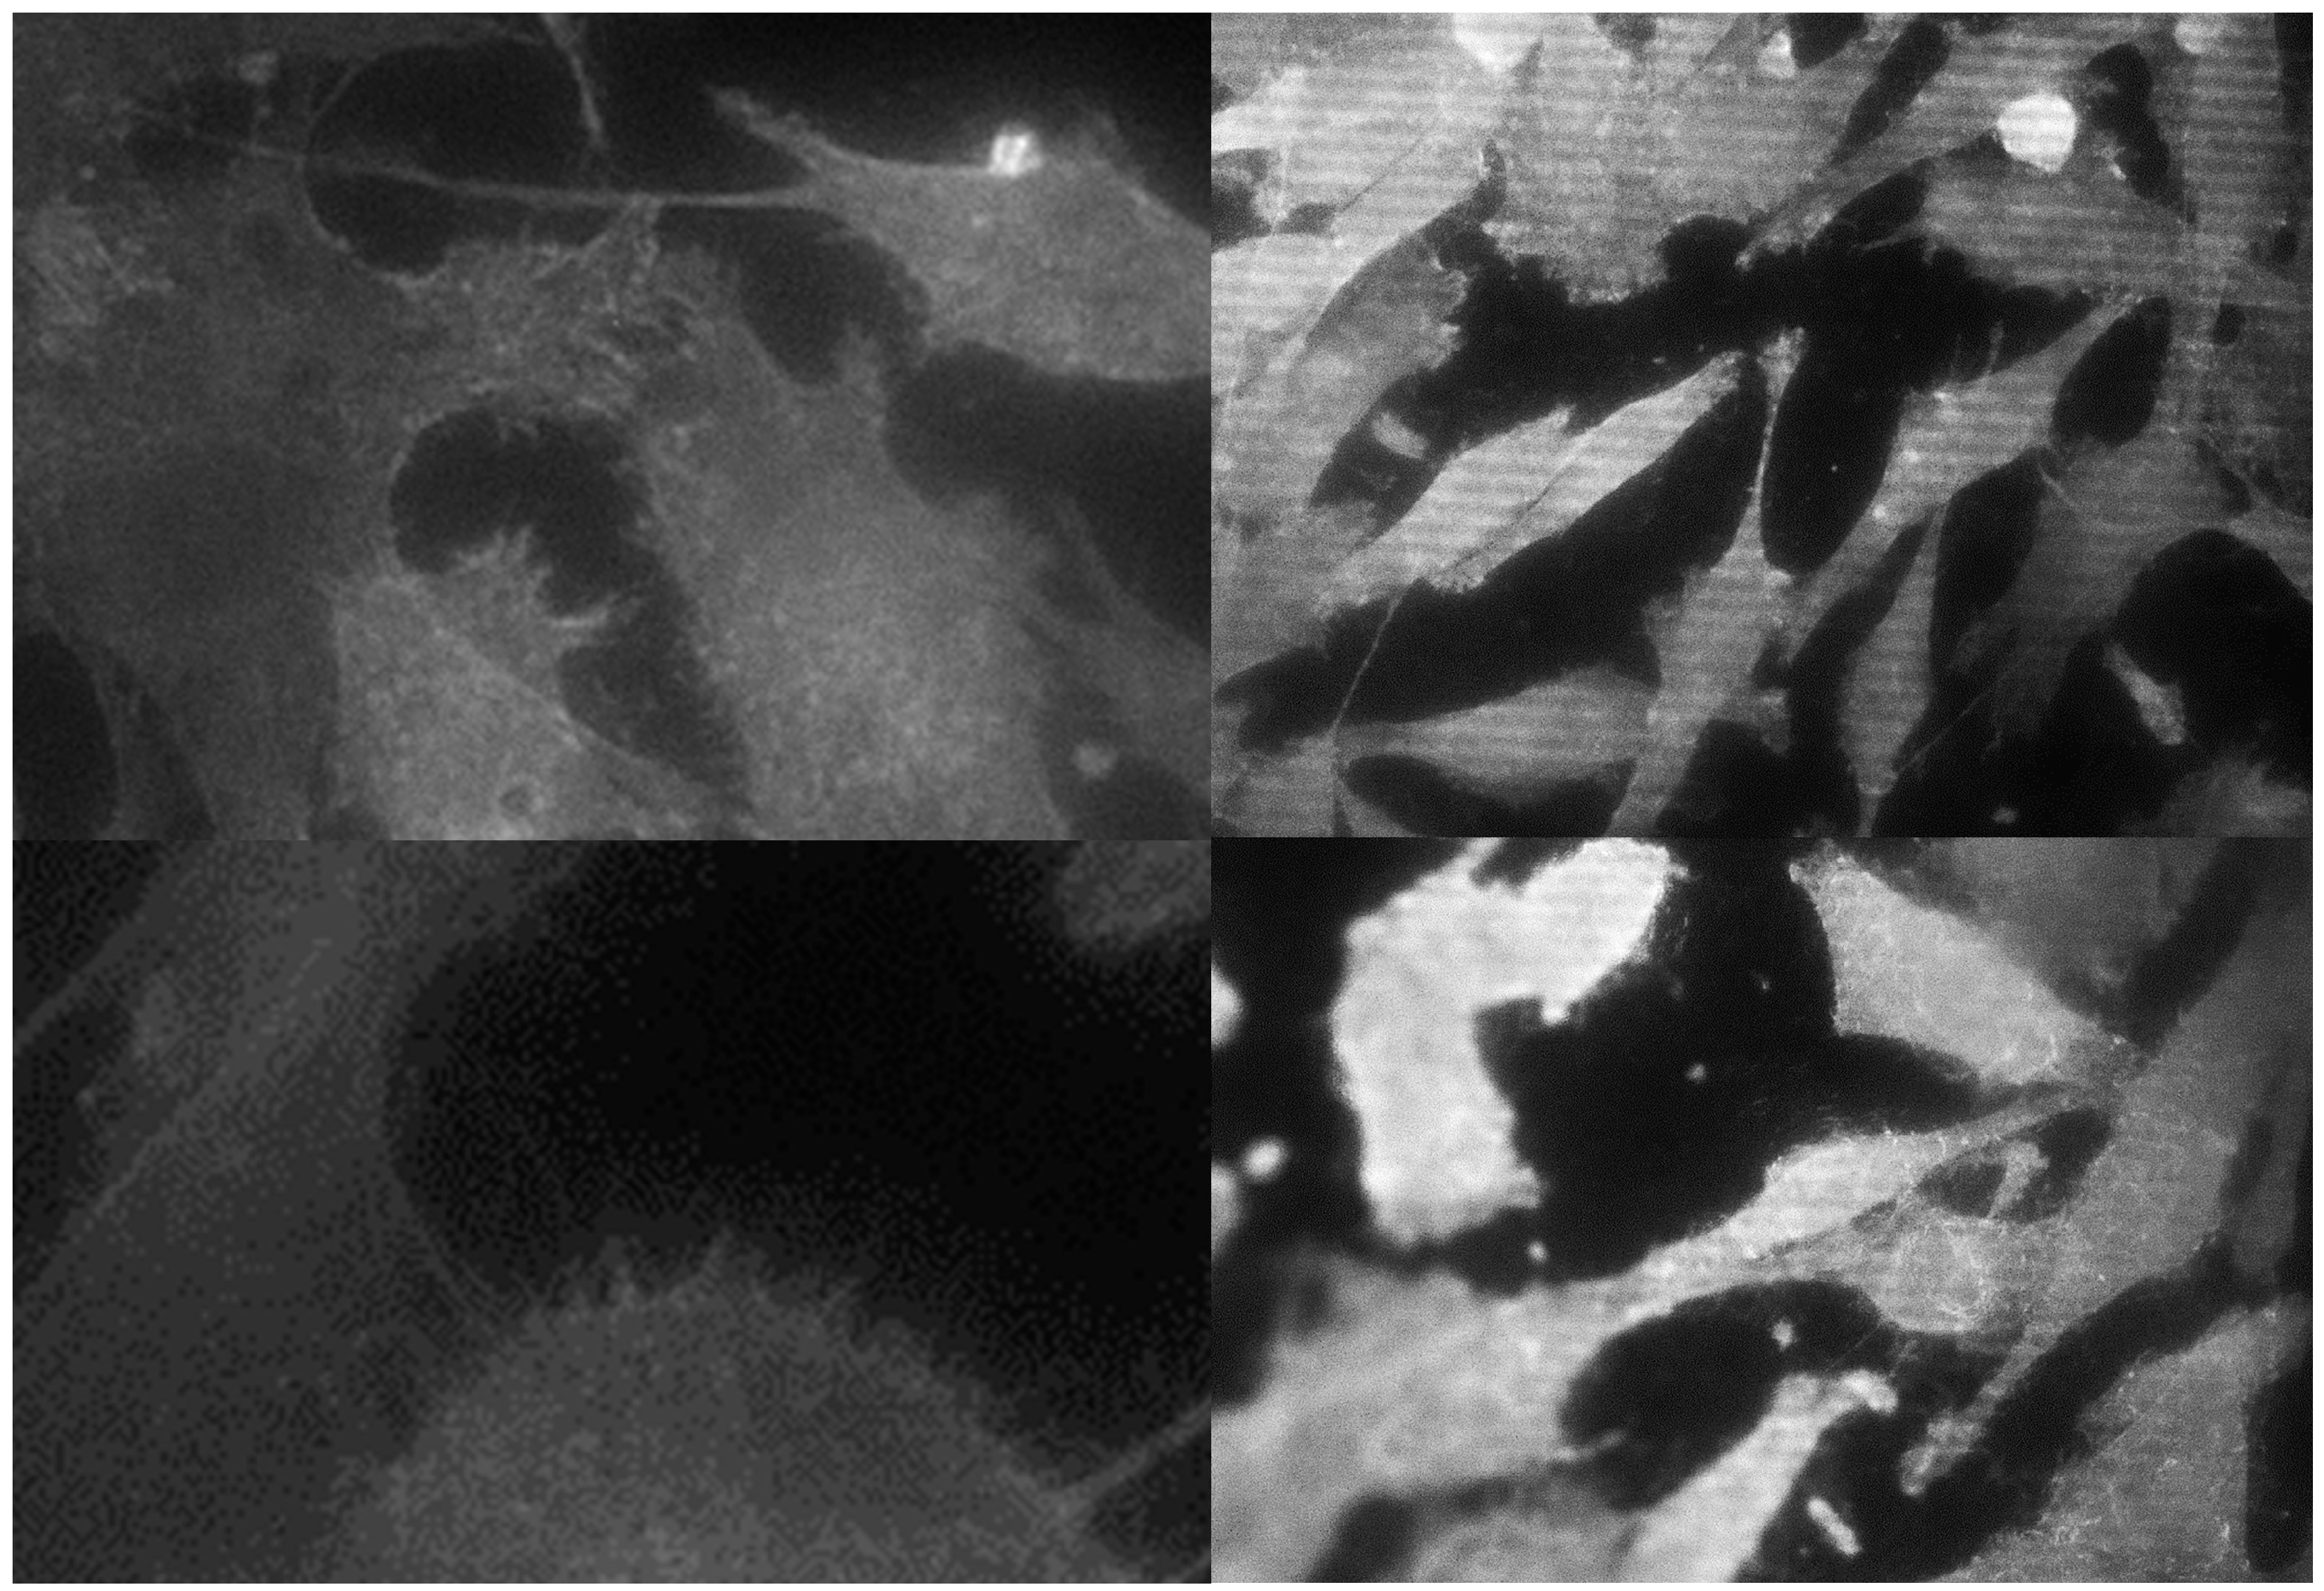

3.2. Morphological Analysis of Cells

| Cell Parameter | Titanium IV (GR4NT) | Titanium IV (GR4TR) | Titanium V (GR5NT) | Titanium V (GR5TR) |

|---|---|---|---|---|

| AREA (µm2) | 430 ± 208 a | 1212 ± 412 b | 525 ± 184 c | 1474 ± 425 abc |

| CIRCULARITY | 0.42 ± 0.02 ab | 0.38 ± 0.03 c | 0.30 ± 0.03 acd | 0.34 ± 0.01 b |